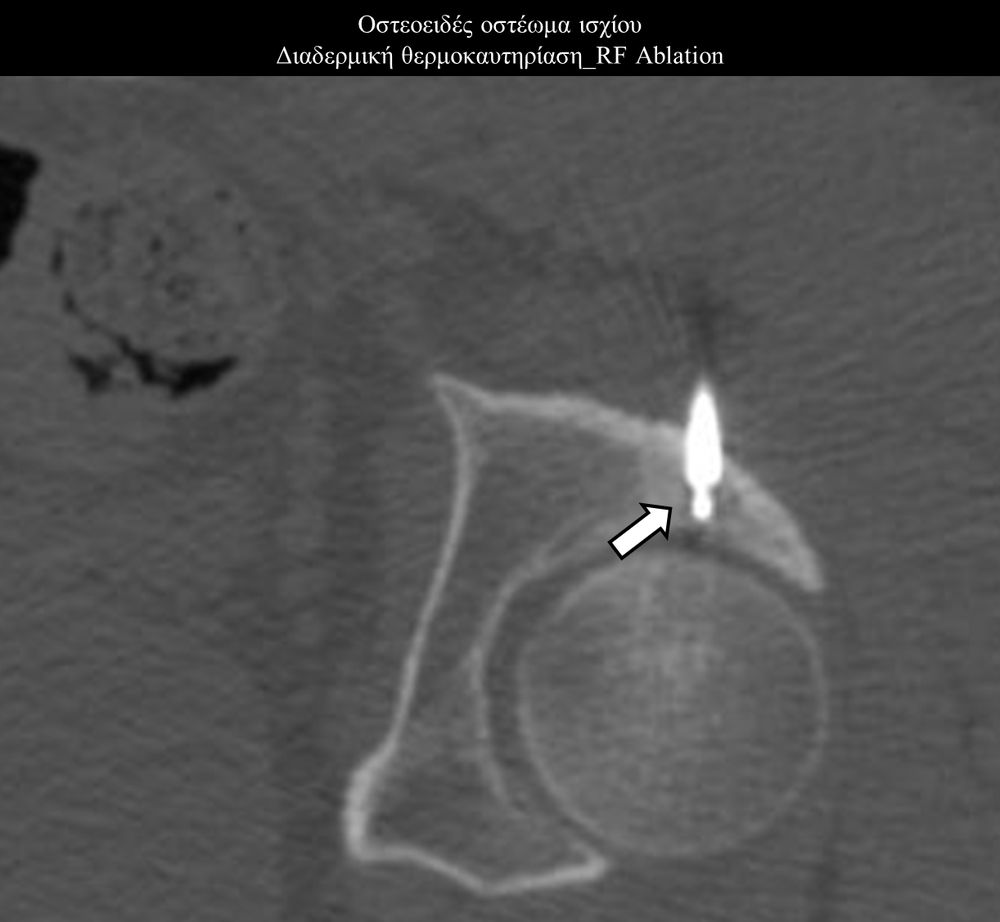

Πρόκειται για την πιο σύγχρονη τοπική θεραπεία όγκων του ήπατος, του νεφρού, του πνεύμονα, των οστών και των όγκων μαλακών μορίων. Παθοφυσιολογικά βασίζεται στην τοπική καταστροφή των καρκινικών κυττάρων με τη δημιουργία ιδιαίτερα υψηλών θερμοκρασιών εντός του όγκου. Αυτό επιτυγχάνεται με τοποθέτηση ειδικών ηλεκτροδίων εντός του όγκου υπό ακτινολογική καθοδήγηση (αξονικός τομογράφος ή υπέρηχος). Τα ηλεκτρόδια αυτά παράγουν υψηλή θερμοκρασία είτε με τη βοήθεια ραδιοσυχνοτήτων (RFablation), είτε με τη βοήθεια μικροκυμάτων (MWablation) και προκαλούν πηκτική νέκρωση των καρκινικών κυττάρων χωρίς να επηρεάζουν τα φυσιολογικά κύτταρα.Το αποτέλεσμα είναι μόνιμο.